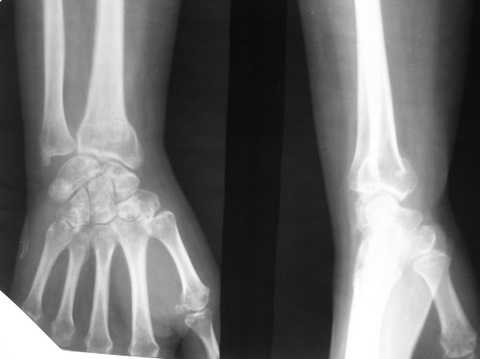

Видимо там был оскольчатый перелом луча и шиловидного отростка

локтевой кости.

В гипсовом повязке наблюдалось вторичное смещение костных отломков по длине (при передне-заднем рентгенограмме), и при боковй проекции видно смещение отломка в дорсальном направлении и таким

образом последный дает компрессию нервов в лучезапястном канале (типа синд. Зудека)

Это видно и клинически.

Этого синдрома купировать почти невозможно на долгий срок, потому что идет постоянная компрессия в канале. остеопопроз это из-за нарушения

иннерваций область кисти.

предлагаем открытую репозицию костных отломков и фиксация спицами